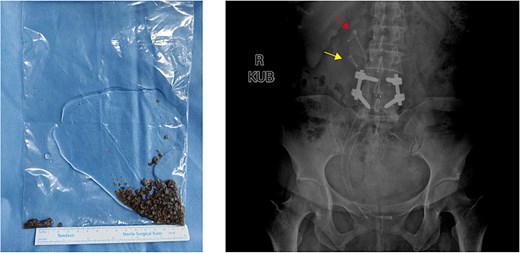

Ureteroscopy via the right ureteral orifice a found no stones and a DJ stent was placed after the examination. Ureteroscopy via the right ureteral orifice b found cystic dilation in the lower segment of the ureter, with a large number of stones within the lower segment of the ureter (Fig. 2). No stone was observed in the upper segment of the right ureter. The endoscope was exited with the guide wire retained, and the Y-type ureteral access sheaths (UAS) (ClearPetra Nephrostomy Access Sheath Set,16/18Fr × 15 cm) were inserted along the guide wire to expand the ureteral orifice. The 16Fr Sheath was retained as the working channel (Fig. 3).

Intraoperative images revealing duplex ureter with ureterocele harboring multiple large stones. Multiple stones were discovered at the opening of ureter b and the surgery was assisted by UAS.

Holmium laser was used for lithotripsy, and the fragments were removed by negative pressure suction. Another DJ stent was placed via orifice b. The total operation time was 153 min. Postoperative KUB confirmed complete lithotripsy and correct stent in the duplex ureters (Fig. 4). The patient was discharged 3 days after surgery. All DJ stents were removed 1 month later without complications. The patient declined further examination and treatment for kidney stones and ureteral anomalies. No discomfort was reported during 6-month follow-up.